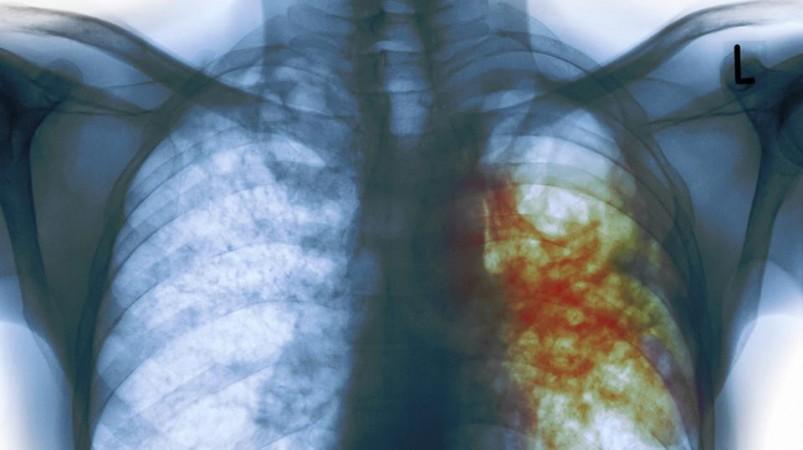

TB primarily affects the lungs but the same bacteria can also cause Bone TB. Similarly, it can spread to other parts of the body through the blood stream. The symptoms of Spine or Bone TB include pain in the joints or lower back.

March 24 is celebrated as World Tuberculosis Day across the globe. The doctors have observed a spike in the number of TB afflicted people in the city of Mumbai, India. This year's motto is "Unite to end TB".